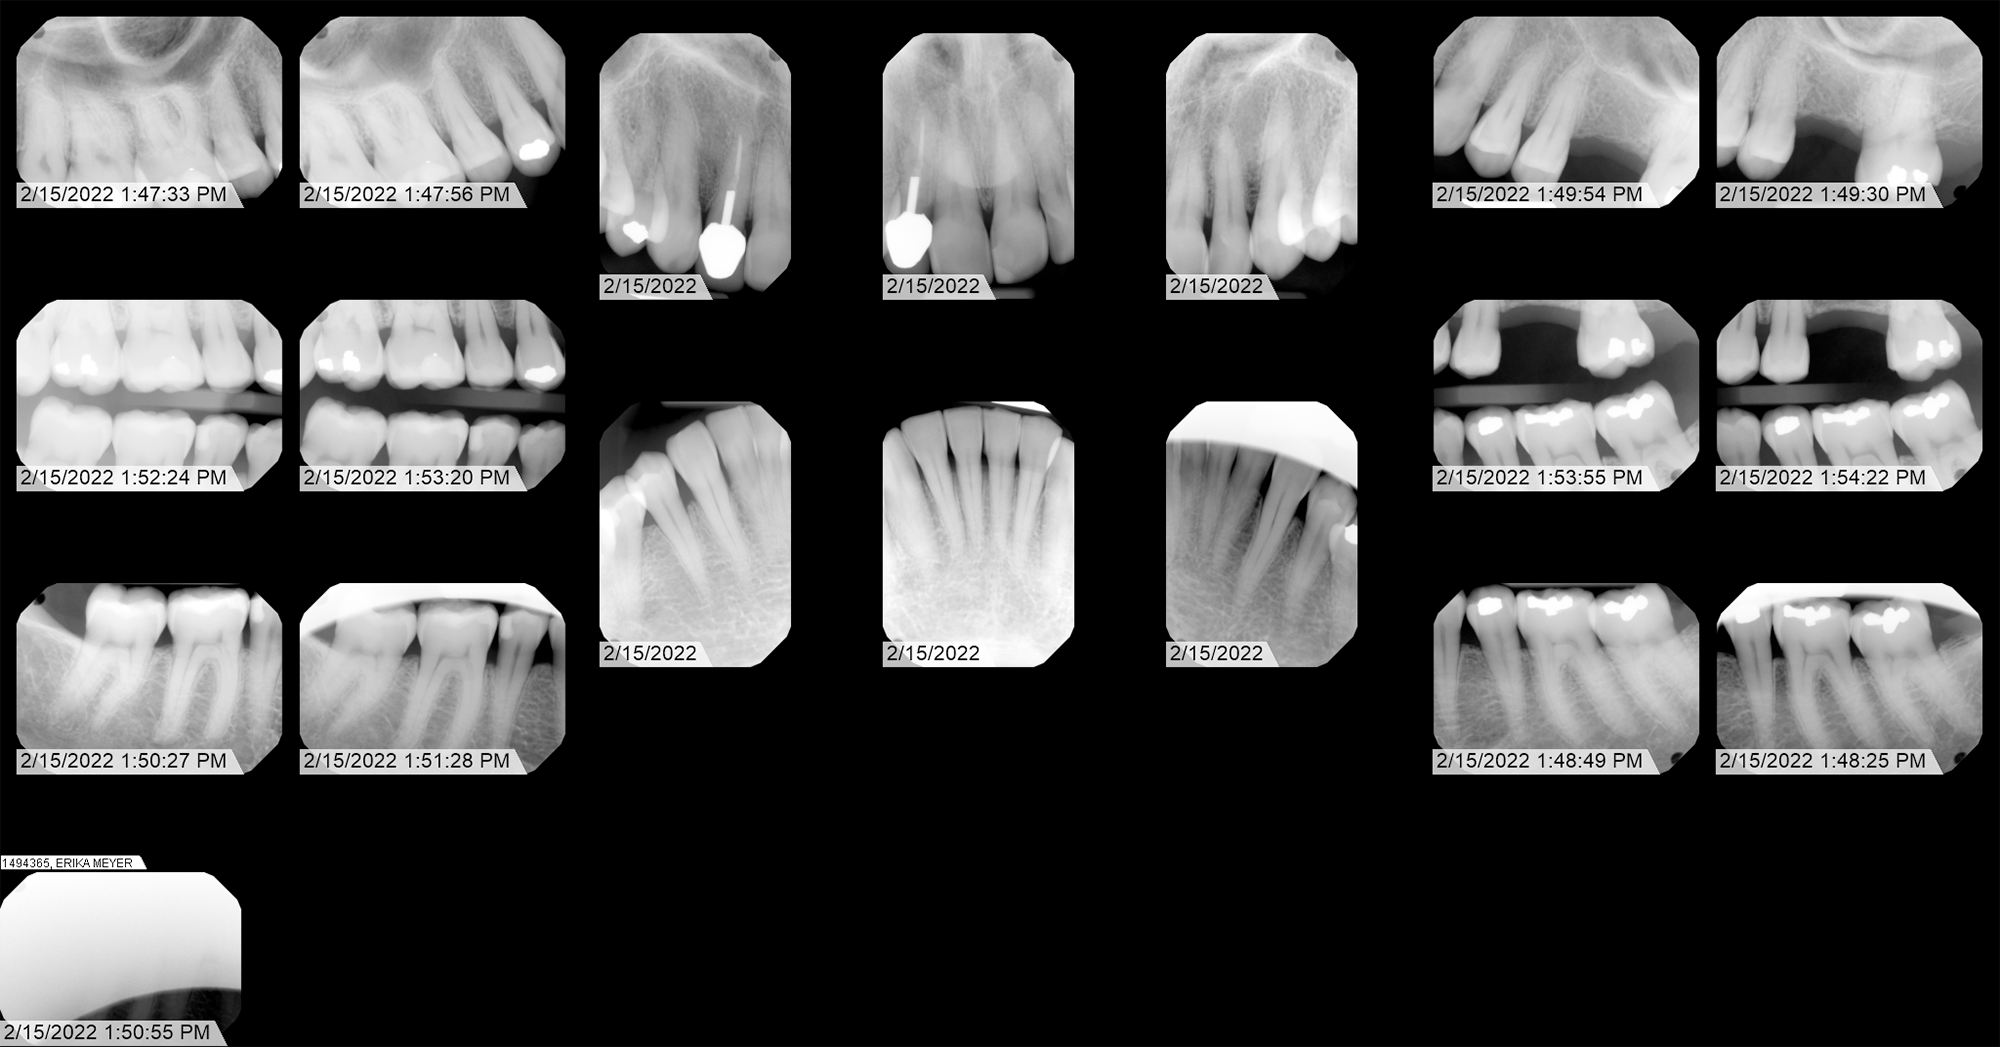

The significance of this radiograph is further reinforced by a history of institutional resistance encountered during attempts at verification. Despite significant effort throughout 2022, I was unable to obtain original DICOM files from either Advantage Dental or Roots Dental. However, in 2026 I was able to locate and cite the federal and state laws requiring them to provide me with that information: HIPAA (45 CFR § 164.524) and Oregon Administrative Rule (OAR) 818-012-0030. As of this writing Advantage Dental has provided me with those files, and to their credit, they did so quickly. Willamette Dental has also provided DICOM files, giving historical perspective. Roots dental did not provide DICOM or original files - and I believe there is a reason for this (to be continued...)

Under the principles established by the 21st Century Cures Act and SWGDE forensic standards, original DICOM data is considered the "Primary Evidence." Prior to this year, both Advantage Dental and Roots Dental insisted on substituting lower-resolution exports, effectively preventing the authentication of sensor-level metadata.

Secondary Exhibits

Dental map showing numbered teeth. Tooth 14 extracted Jan 10, 2020